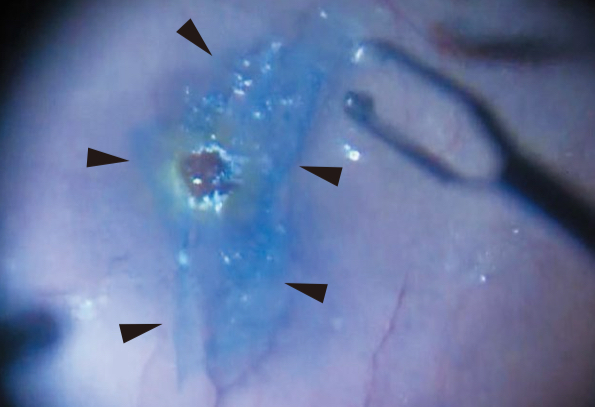

黄斑円孔というのは、網膜の中心部の黄斑に穴ができてしまう病気で、中心部の見えにくさを生じ、そのままにしておくと高度の視力障害を来してしまいます。治療としては、硝子体手術で硝子体を取り除き、中心部の網膜の一番内側の内境界膜(ILM;内境界膜)を剥がし、眼の中に医療用のガスを入れ、ガスが黄斑の穴を押し付けることで円孔が閉鎖させることを目的とした手術を行います。

今日、手術の患者さんは昨年10月に当院で白内障手術を受けていただいた50代の男性の方でしたが、眼の長さ(眼軸長)が32mmを超える強度近視の眼で、再発が起こりやすそうだったので、ILMは完全に剥がさずに少しだけ残して円孔の上に乗せるようにしてきました(inverted flap technic)を行ってきました。これでなんとか治ってくれるといいなと思います。